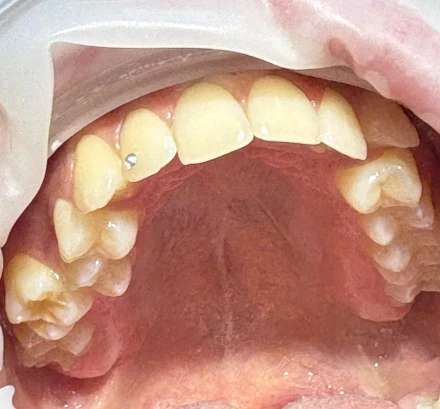

1h 30m 300 BGN / 153,39 €

Добавлен 4 месяца назад